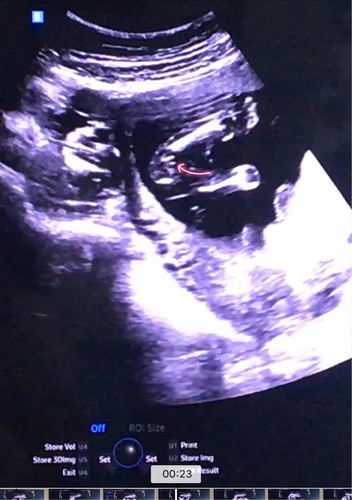

วันนี้ไปซาว์ด 16w คุณหมอบอกว่า ยังเห็นเพศไม่ชัดเท่าไร ให้มาดูอีกทีเดือนหน้า แต่หมอคาดว่าน่าจะผู้หญิง แม่ๆว่าหญิงไหมคะ บ้านนี้อยากได้หญิงมากคะ

ก็เหมือนจะเป็นกลีบอยู่นะแม่ รอหมอคอนเฟิร์มนะคะ